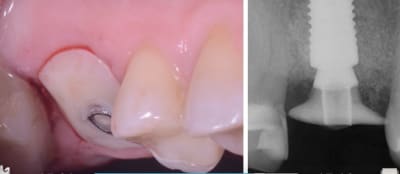

C’est ça , une sorte de pilier/vis de cicatrisation enduite de compo qui épouse la forme de ton ancienne dent dans sa portion cervicale

> C’est ça , une sorte de pilier/vis de cicatrisation enduite de compo qui épouse

> la forme de ton ancienne dent dans sa portion cervicale

le SSA çà marche super bien pour les EII sur les PM et molaires, à condition de ne pas avoir de défaut osseux, en plus pour la prothèse finale c'est top car tu conserves l'architecture gingivale de la dent initiale...